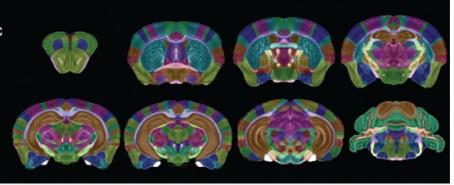

Imaging Biomarkers for Alzheimer’s Disease Using Magnetic Resonance Microscopy

BIAC co-authors Alex Badea (lead) and Jacques Stout have a book chapter "Imaging Biomarkers for Alzheimer’s Disease Using Magnetic Resonance Microscopy" published in a new edited volume Magnetic Resonance Microscopy: Instrumentation and Applications in Engineering, Life Science, and Energy Research from Wiley.